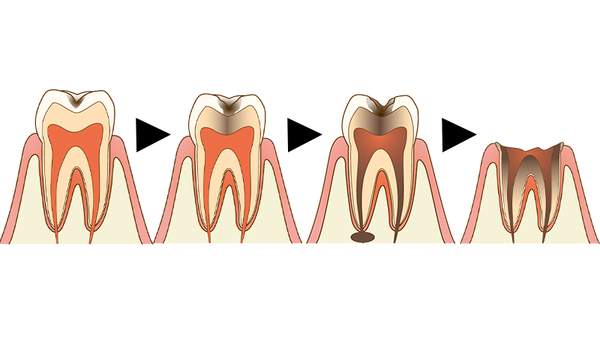

黒い虫歯があるが、エナメル室内の浅い虫歯です。

虫歯がエナメル質を超えて中まで進行しています。

虫歯が神経に達してます。

虫歯が神経まで達して歯冠が崩壊しています。